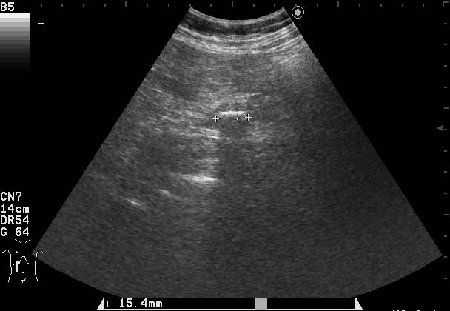

Сонограммы холедоха:

- Поперечный скан холедоха

На верхнем снимке можно предположить внутрипросветную опухоль в холедохе.

В сущности, ответ правильный уже был - это опухоль холедоха с инкрустацией ее ткани.

Благодаря такой необычной презентации опухоль была ошибочно принята за камень холедоха.

Спасибо!Очень интересный случай,смотрю уже который раз.Можно ошибиться,но "камень"обволочен мягкотканной структурой-гипоэхогеной,раздвигая стенки коледоха,типа "веретено".Так,что коллега права-опухоль